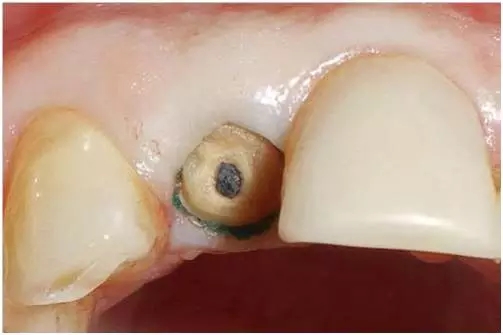

口內(nèi)檢查(圖1至4);

圖4:外傷9天后的臨床檢查:12牙牙冠在釉牙骨質(zhì)界水平處折斷。在使用牙齦收縮線后可以評(píng)估整個(gè)斷面。